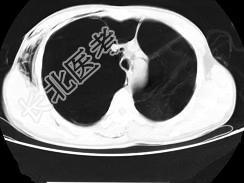

- 单项选择题男,32岁, 被车撞伤后1小时,请结合影像图像选择其最可能的诊断为 ( )

A、右侧气胸

B、右肺不张

C、右侧气胸并皮下纵隔气肿

D、右侧肺大疱并皮下纵隔气肿

E、支气管断裂